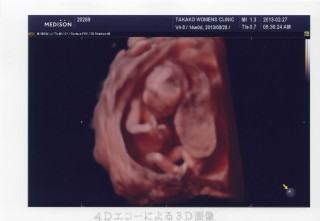

今日から腹部エコーです!初めて顔を見せてくれました!ものすごいカメラ目線です(笑)モニョモニュ動いて可愛かったです!

早く胎動感じたいなぁ~☆性別はまだ分からなかったです。次がまた4週間後…。長いよ~!